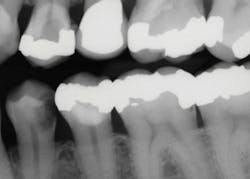

Use the following technique to remove deep caries for indirect restorations, such as crowns and onlays (figures 2–4):

Figure 3: The second molar had about one-half of the coronal tooth structure removed and required a resin-based composite buildup. The first premolar had only a Class I defect and received a filler of bonded compomer (Dyract). The canine received a fiber-reinforced post, two pure titanium pins on the lingual (Filpins from Filhol Dental), and a resin-based composite coronal buildup.